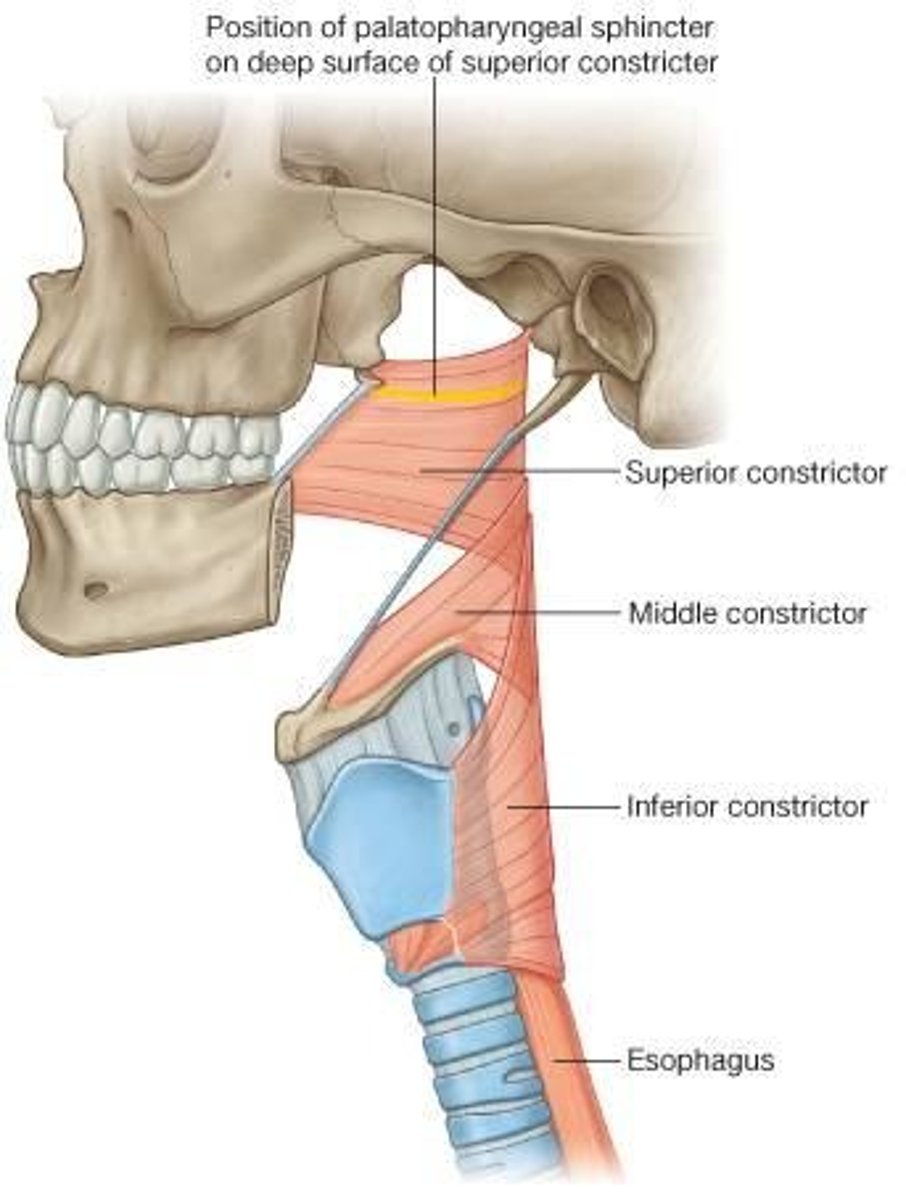

Superior Constrictor Description

Weakest, but most complex of the three

Forms nasopharyngeal and upper

oropharyngeal walls

Origin - sphenoid, mandible, pterygomandibular ligament

Course - posterior, then medial

Insertion - midline raphe

Action - may contribute to velopharyngeal closure by moving posterior wall of pharynx

anteriorly

Middle Constrictor Description

Somewhat fan shaped

Origin - hyoid bone

Course - fan out posteriorly and medially

Insertion - midline raphe

Action - reduce diameter of pharynx

Inferior Constrictor -

Thyropharyngeus Description

Inferior Constrictor consists of the

Thyropharyngeus and the Cricopharyngeus

Inferior Constrictor is thickest and strongest of constrictor muscles

Thyropharyngeus is the majority of the Inferior Constrictor

Origin -thyroid cartilage

Course - fans out posteriorly and medially

Insertion - midline raphe

Action - reduce diameter pharynx